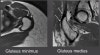

엉덩이 근육은 심부에 있으므로 손상근육의 정확한 위치 파악이 힘들 수 있습니다.